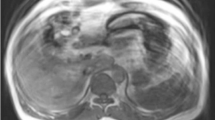

Comprehensive evaluation for most abdominal applications is possible by performing a basic abdominal MRI protocol as illustrated in Fig. 1. In this protocol, the order of pulse sequences is optimized for extracellular space contrast agents. Protocol adjustments are needed when using the hepatocyte-specific contrast agent, gadoxetate disodium (Eovist/Primovist; Bayer HealthCare, Leverkusen, Germany) [1, 2]. The imaging parameters for the pulse sequences in this suggested protocol are listed in Table 1 along with the required protocol adjustments for gadoxetate disodium. Regarding contrast-enhanced protocols, an important point to remember is to administer gadolinium as early as possible, in case the patient cannot finish the exam. This ensures that the 3D pre- and postgadolinium gradient echo sequences, often the most important pulse sequences, are performed (Fig. 1). This is feasible since (as discussed later) only heavily T2-weighted and dual gradient echo sequences need to be performed before gadolinium administration [2].

This is a basic abdominal MRI protocol when using an extracellular space agent and the order of pulse sequence acquisition. This protocol can provide comprehensive evaluation for most abdominal applications. Specific parameters for this protocol are listed in Table 1. 2D two dimensional, 3D three dimensional, ADC apparent diffusion coefficient, BSSFP balanced steady-state free precession, DWI diffusion-weighted imaging, GRE gradient echo, MRCP magnetic resonance cholangiopancreatography, Post dynamic postgadolinium, Pre pregadolinium, T2WI T2-weighted image